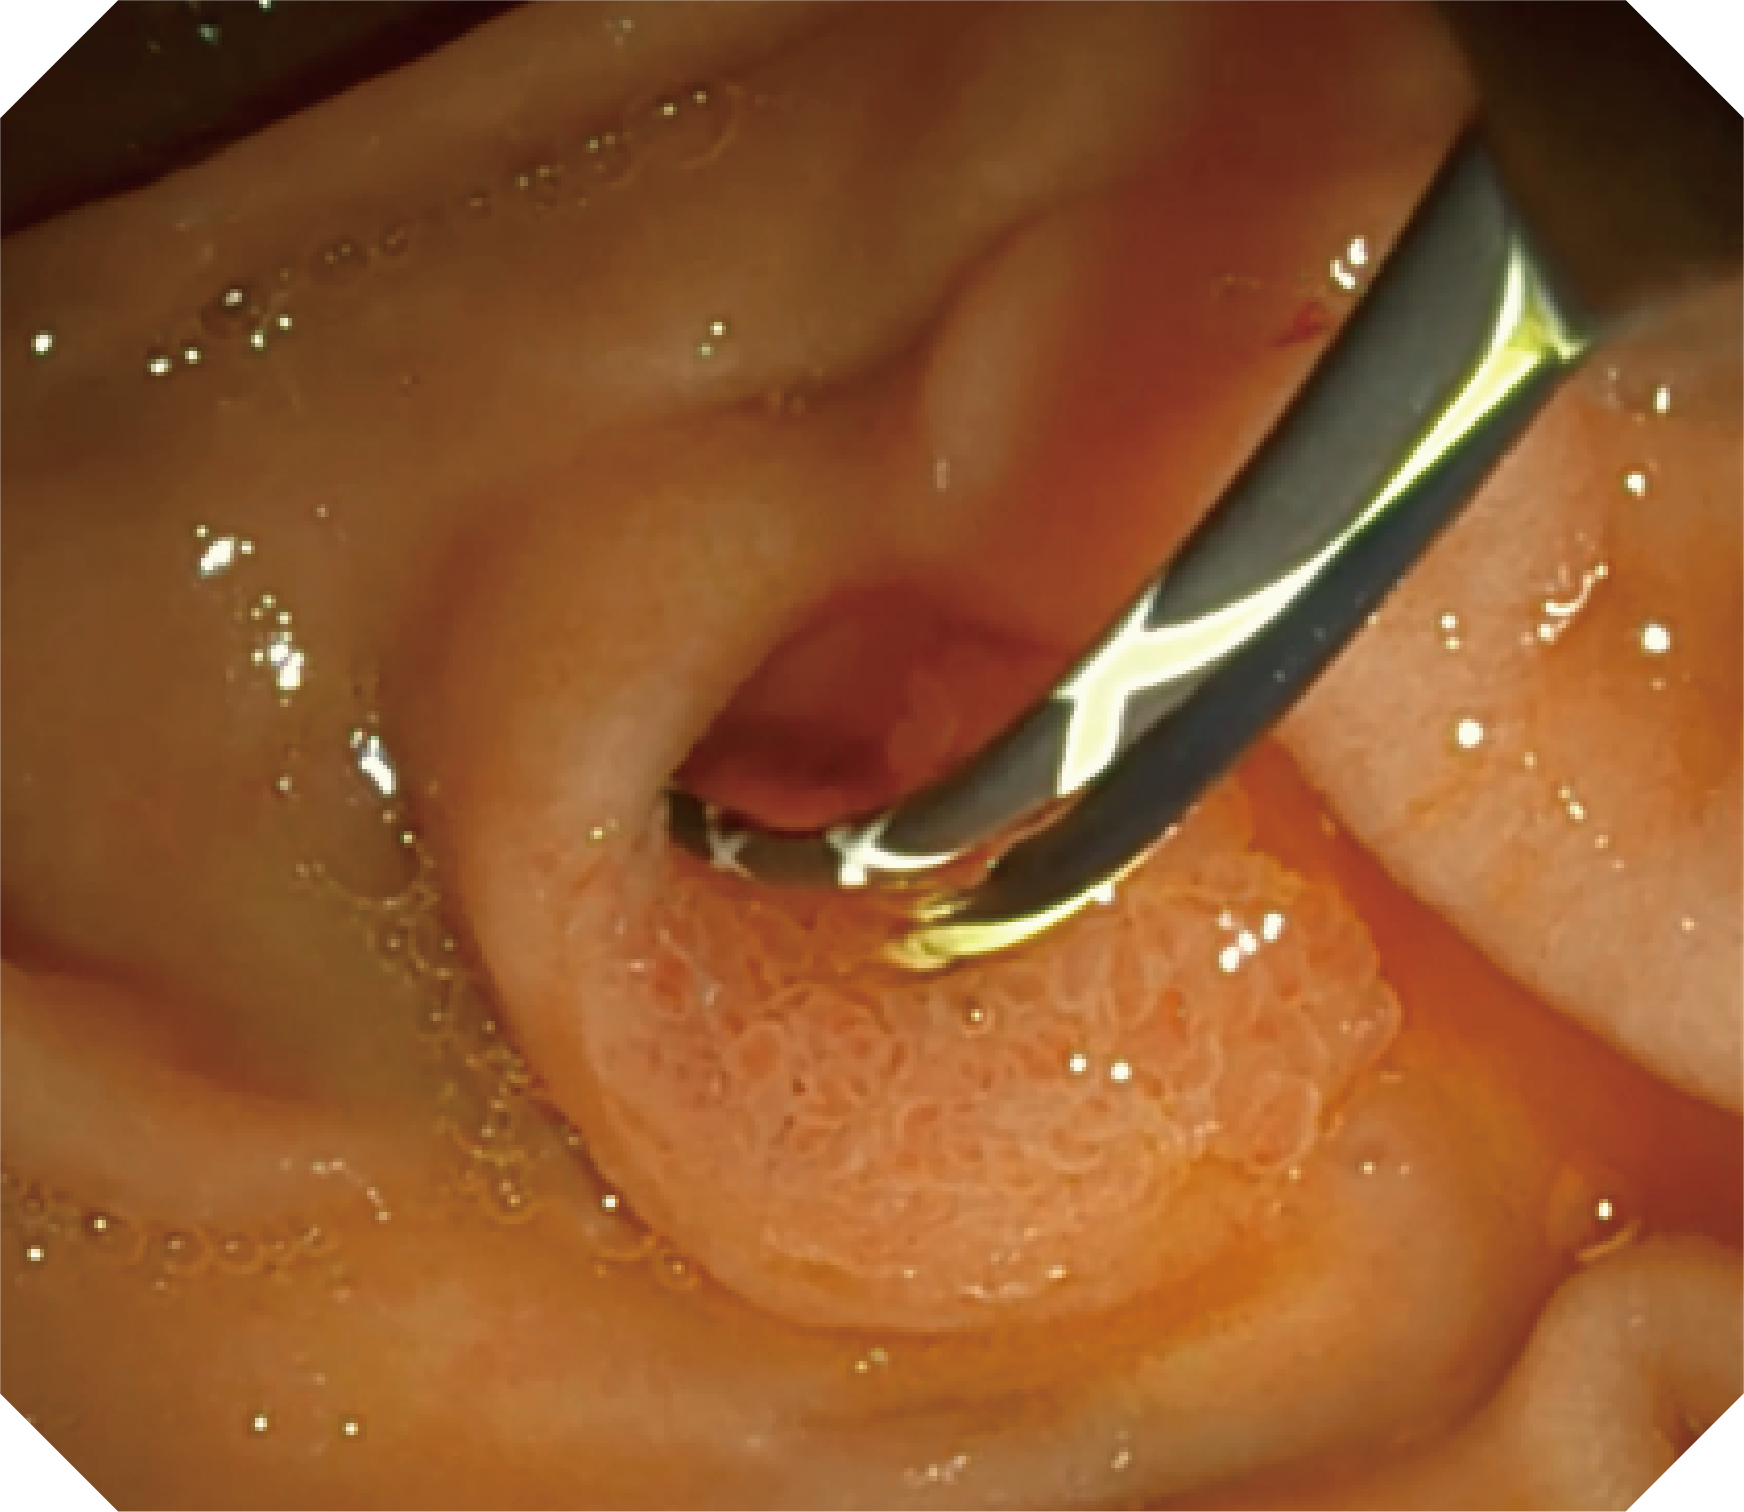

4.2mm大钳道,器械交换更顺畅

优异的手术器械抬举性